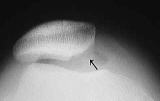

下記X線写真例は内側が骨と骨が接触し極めて高度の変形性膝関節症です。手術所見では内側の軟骨は消失し軟骨下骨が露呈(矢印)。外側はほぼ正常な軟骨です。

内側軟骨消失と硬化

内側軟骨消失と硬化